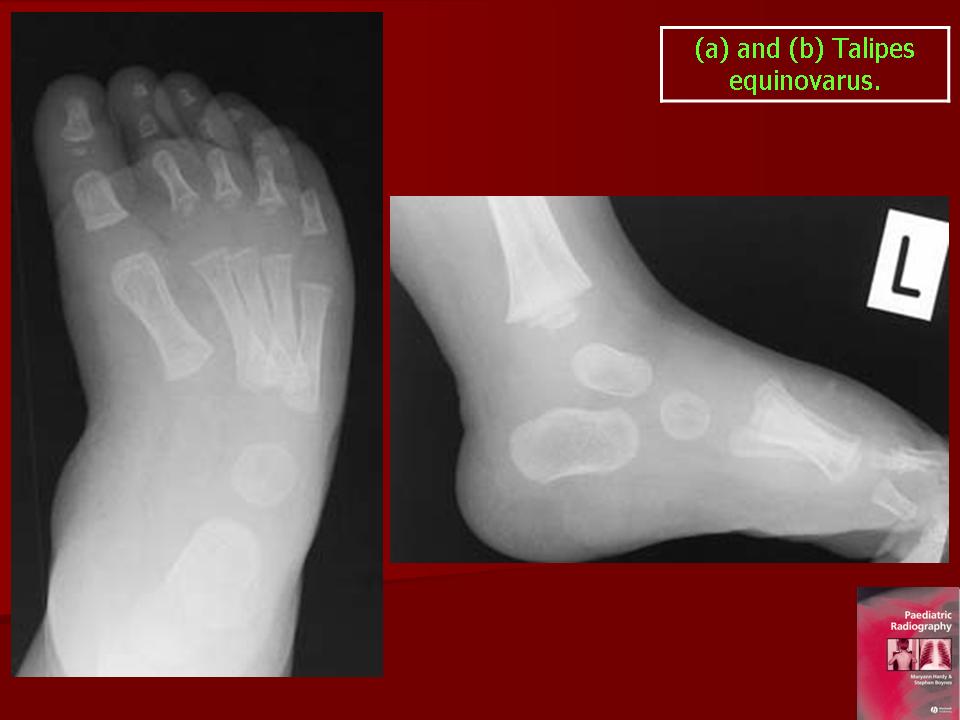

Эквиноварусная стопа